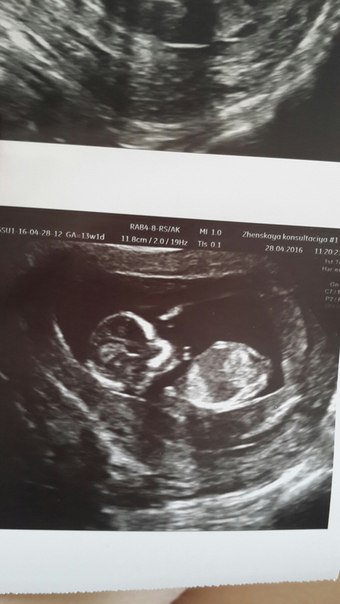

Результаты: УЗИ, КТГ, доплера, скринингаДД, девушки! Вот и настал этот волнительный день. Пришла на узи так волновалась что чуть в обморок не рухнула)))Ниже результаты УЗИ, кровь только сдала. Есть вопросы..

ТВП и Носовая кость вроде в норме.. Анатомия эмбриона вроде все определяется в норме.Далее идет особенности стоения плода. Кишечник и глазницы определяются(?)почему тут написано) Далее написано - 2 СОСУДА. Это пуповина???Должно же быть 3???

Ну и волнует что до этого ставили кревое предлежание..теперь центральное..